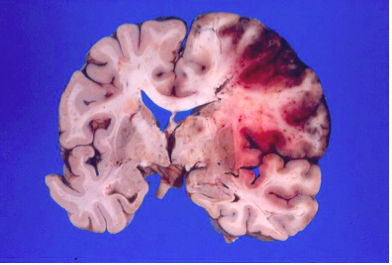

What does this image show?

cerebral edema:

An acute stroke (left) is characterized by edema. The infarcted side is larger than the opposite hemisphere.